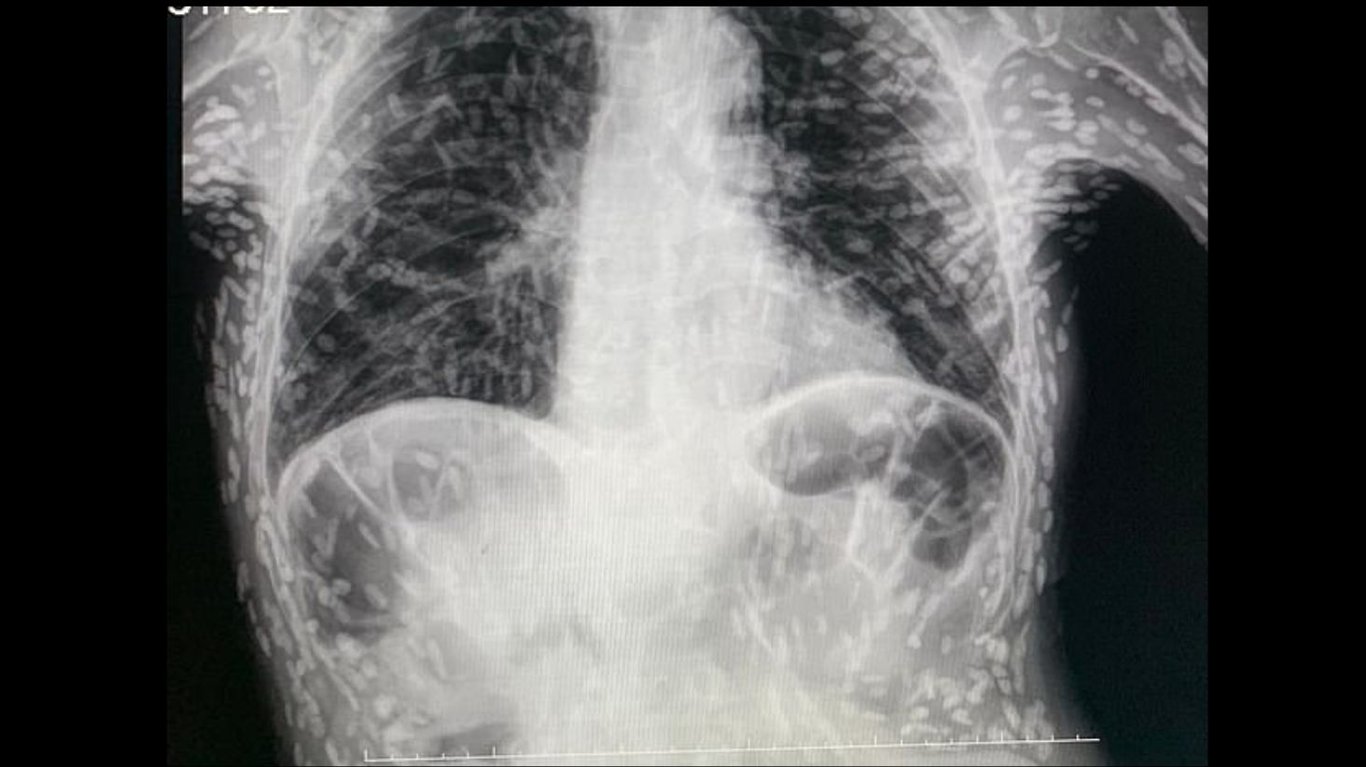

Бразильський лікар опублікував шокуючі рентгенівські знімки на якому видно, що тіло чоловіка у рештках десятків личинок стрічкових черв'яків. Пацієнт розповів, що його турбував тільки кашель

"Шокуючі знімки показують, як пацієнт, який звернувся по допомогу через постійний кашель, був пронизаний рештками десятків личинок стрічкових черв'яків. На рентгенівському знімку шлунку, опублікованому бразильським лікарем, видно сотні яскравих плям, кожна з яких представляє собою кальциновані рештки паразита. Цей стан, який називається цистицеркозом, виникає, коли личинки виду ціп'яка, який зазвичай живе в кишечнику, потрапляють у такі тканини, як м'язи або мозок. Там вони утворюють тверді вузликоподібні кісти, які можуть відчуватися як шишки під шкірою", — йдеться в повідомленні.

Кожна точка — кіста, викликана личинками стрічкових черв'яків. Фото: Twitter Доктора Вітора Боріна де Соуза.